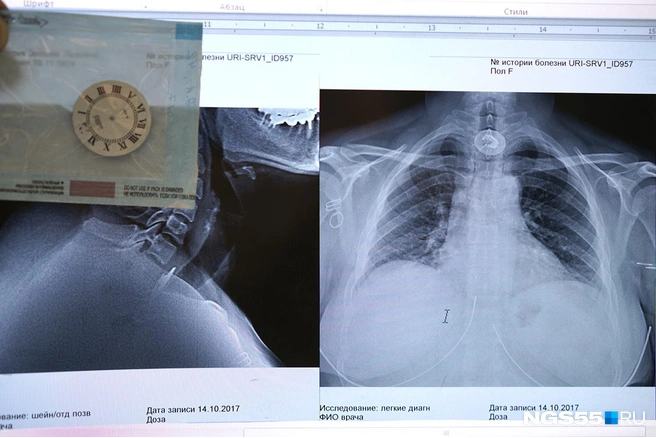

— Томография показала достаточно крупное твёрдое тело. Тут какие варианты — оперировать и удалять часть лёгкого, уменьшая дыхательный объём, или извлечь с помощью фиброэндоскопа, — рассказывает Альгис Хасанов.

Врачи извлекают из лёгких много интересного. Из более-менее предсказуемого — ножи, пульки от воздушек и картечь от дробовиков, арматура... Всё это никогда не извлекают из пострадавших на месте, а бинтуют поверху и в таком виде доставляют хирургам.

Отдельная история — куриные кости, свечки от торта, чайные ложки... Попадался даже блистер от таблеток. Благополучно, как тот зуб, извлекаются не всегда — часто всё-таки приходится резать, если крупный предмет зашёл слишком далеко.